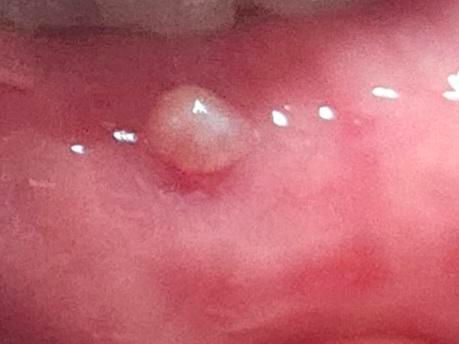

교정 철솨에 잇몸이 닿아서 이상한 게 생겼어요

교정 중에 철솨에 계속 닿아서 뭐가 났었는데 보통 왁스 붙이면 바로 괜찮아지는데 이번엔 안 괜찮아져요..

교정철사의 잇몸이 자극이 되면 해당 부위에 물집 같은 것이 생길 수 있습니다. 점액종이라고 하는데 크게 문제가 되진 않습니다.

교정 와이어에 잇몸이 계속 자극을 받아서 염증이 생긴거 같으니 와이어를 체크 받아보시는게 좋을것같습니다.

지속적인 자극으로 잇몸 상피조직이 과증식된 것 같은데 검사해보고 별다른 병적양상이 아니라면 절제해주면 됩니다